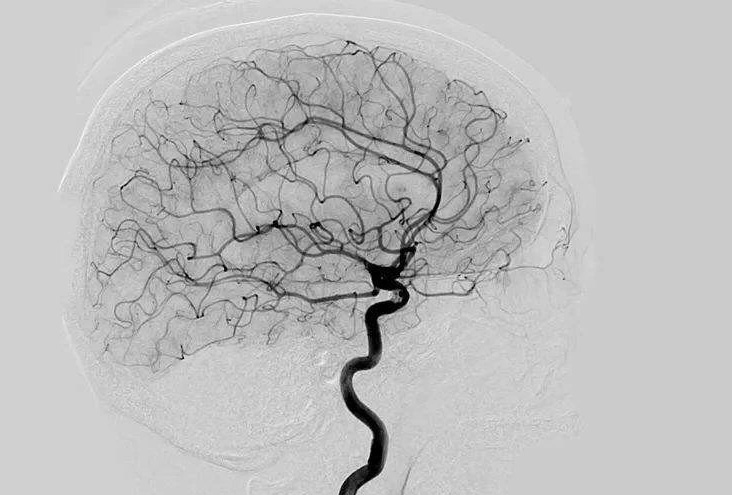

Digital Subtraction Angiography 血管造影機(jī)應(yīng)注意什么?

Digital Subtraction Angiography 血管造影機(jī)又稱數(shù)字減影血管造影機(jī),是通過電子計算機(jī)進(jìn)行輔助成像的血管造影方法,應(yīng)用計算機(jī)程序進(jìn)行兩次成像完成的。在注人造影劑之前,第一次成像工作,圖像轉(zhuǎn)成數(shù)字信號儲存,注人造影劑后,再次成像并轉(zhuǎn)換成數(shù)字信號,兩次數(shù)字相減,消除相同的信號,得到只有造影劑的血管圖像。臨床主要應(yīng)用于冠心病、心律失常、瓣膜病和先天性心臟病的診斷和治療。